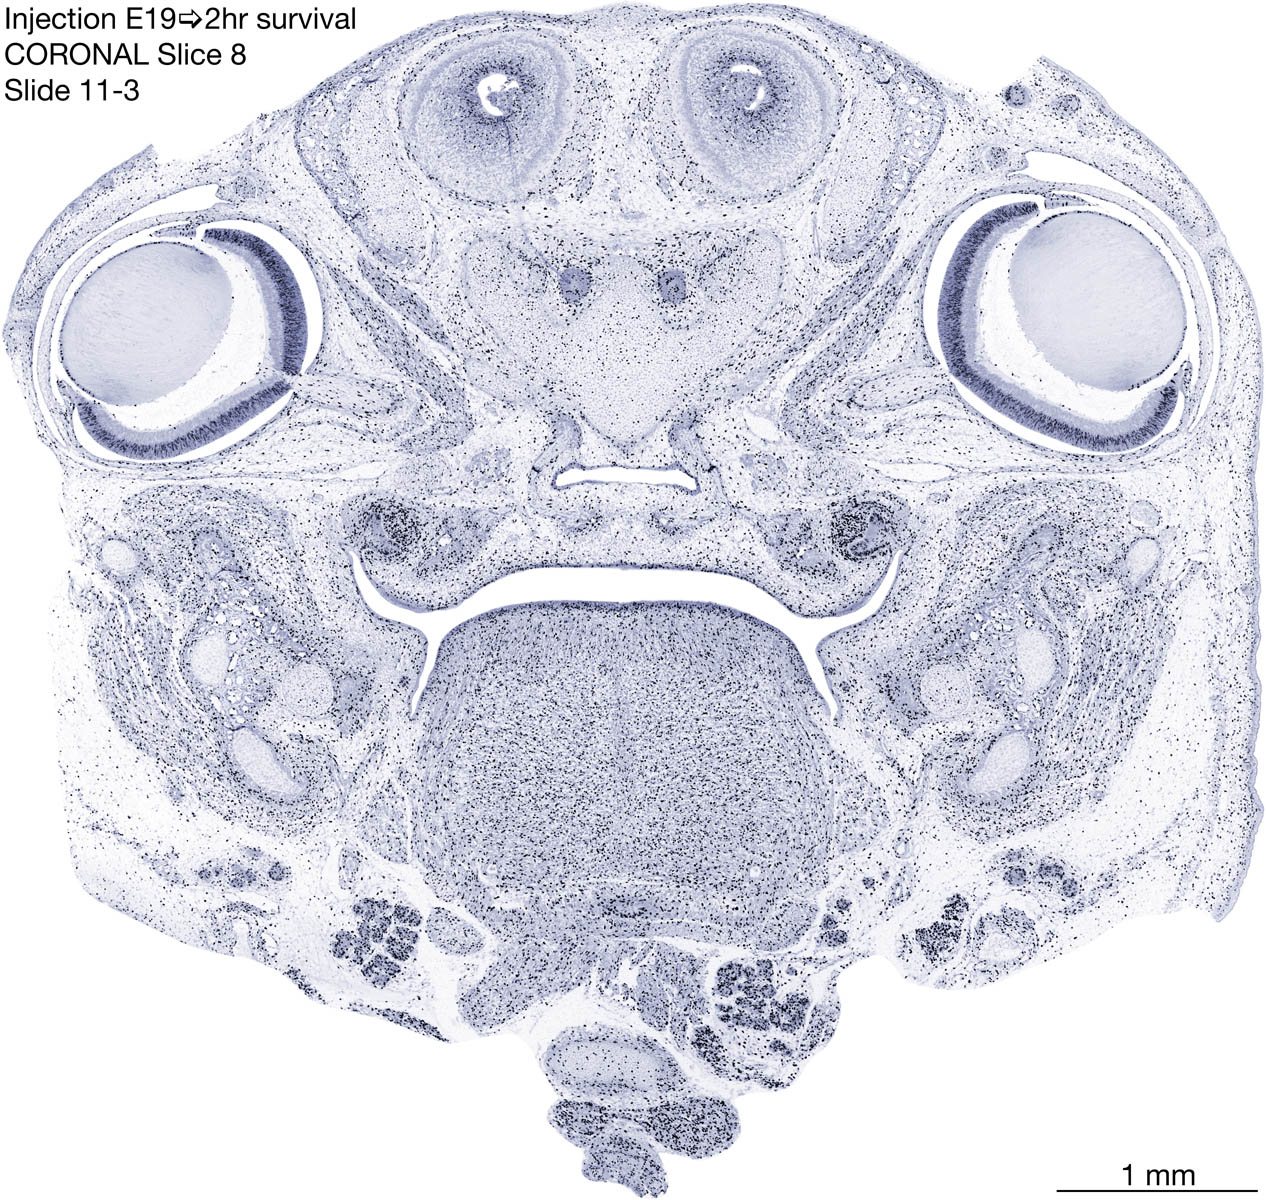

E19 2hr Survival Archived Images-Coronal The following images are from a paraffin-embedded coronally-sectioned head of an E19 rat embryo exposed to tritiated thymidine 2 hours before death. Download: Large | High Res Download: Large | High Res Download: Large | High Res Download: Large | High Res Download: Large | High Res Download: Large | High Res Download: Large | High Res Download: Large | High Res Download: Large | High Res Download: Large | High Res Download: Large | High Res Download: Large | High Res Download: Large | High Res Download: Large | High Res Download: Large | High Res Download: Large | High Res Download: Large | High Res Download: Large | High Res Download: Large | High Res Download: Large | High Res Download: Large | High Res Download: Large | High Res Download: Large | High Res Download: Large | High Res Download: Large | High Res Download: Large | High Res Download: Large | High Res Download: Large | High Res Download: Large | High Res Download: Large | High Res Download: Large | High Res Download: Large | High Res Download: Large | High Res Download: Large | High Res Download: Large | High Res Download: Large | High Res Download: Large | High Res Download: Large | High Res Download: Large | High Res Download: Large | High Res Download: Large | High Res Download: Large | High Res Download: Large | High Res Download: Large | High Res Download: Large | High Res Download: Large | High Res Download: Large | High Res Download: Large | High Res Download: Large | High Res Download: Large | High Res Download: Large | High Res Download: Large | High Res Download: Large | High Res Download: Large | High Res Download: Large | High Res Download: Large | High Res Download: Large | High Res Download: Large | High Res Download: Large | High Res Download: Large | High Res Download: Large | High Res Download: Large | High Res Download: Large | High Res Download: Large | High Res Download: Large | High Res Download: Large | High Res Download: Large | High Res Download: Large | High Res Download: Large | High Res Download: Large | High Res Download: Large | High Res Download: Large | High Res Download: Large | High Res Download: Large | High Res Download: Large | High Res Download: Large | High Res Download: Large | High Res Download: Large | High Res Download: Large | High Res Download: Large | High Res Download: Large | High Res Download: Large | High Res Download: Large | High Res Download: Large | High Res Download: Large | High Res Download: Large | High Res Download: Large | High Res Download: Large | High Res Download: Large | High Res Download: Large | High Res